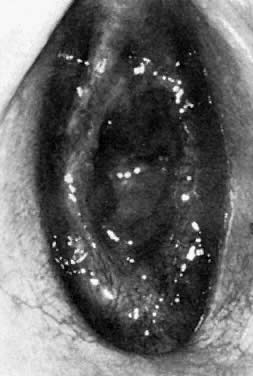

Stronger emphasis is now placed on findings of disturbance of the normal clear lacy hymenal vasculature or loss of the velamentous delicate border, especially posteriorly from 9 to 3 o'clock. Asymmetric tears of the hymen in this area. especially deep stellate tears accompanied by the previously mentioned changes, are highly suspicious. Scarring and attenuation are unequivocal proof of penetration14 (Fig. 1). Straddle injuries or other accidental trauma (e.g., balance beam falls, horseback riding) do not injure the hymen alone and must be accompanied by additional evidence of vulvar trauma to warrant etiologic consideration. 15

Fig. 1. Scarring and attenuation as a result of penetration